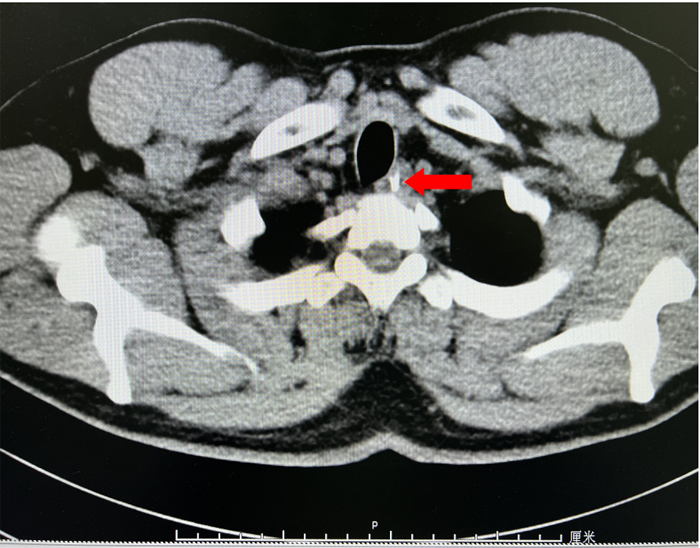

近日,我院李曙晖主任医师在内镜中心护理、麻醉团队密切配合下,通过内镜下食管黏膜剥离术,成功为一辗转3家医院食管异物1周的患者取出3cm鱼刺。12月18日,患者陈某在进食鱼后出现咽部异物感,伴有吞咽痛,19日在当地医院行胸部CT示食管异物待排,胃镜示创伤性食管炎,食管内未见明显异物。3天后,患者咽部异物感等症状无缓解,于我市另一医院复查胸部CT示食管上段异物,再次行胃镜检查示食管黏膜损伤,未见异物。胸外科会诊认为如果外科手术,创伤大,建议患者首选内镜下微创手术。因此,患者慕名前来我院就诊,收住消化内科一病区。为了解鱼刺与周围的关系及是否刺入血管,患者入院后给予完善胸部强化CT,示胸上段管腔内高密度影,考虑食管异物。李曙晖主任医师结合患者病史、2次胃镜结果及胸部CT等,分析认为鱼刺已深深扎入食管壁内,可行食管黏膜剥离术暴露出异物后再行取出。12月28日,李曙晖主任医师在麻醉和护理团队的配合下行胃镜检查,内镜下距门齿18cm可见食管黏膜充血水肿,未见异物,遂用黏膜切开刀切开周围黏膜及肌层,暴露出异物顶端,再用鳄口钳钳住鱼刺顶端,顺利取出一枚长3cm多的鱼刺,看到大部分鱼刺扎入食管壁。术后对症治疗后,患者现已痊愈出院。李曙晖主任医师提醒,食管异物可发生在任何年龄段,而且异物种类多样,以鱼刺、肉骨最为常见。一旦发生异物卡喉或消化道异物,用醋、团饭、菜叶等吞咽均不可取,这些做法最大的可能是将鱼刺越压越紧、扎得更深,如果是比较大的刺还有可能刺破食管或血管,危害更大。正确的处理是立即停止进食,及时就医,不能抱有侥幸心理。